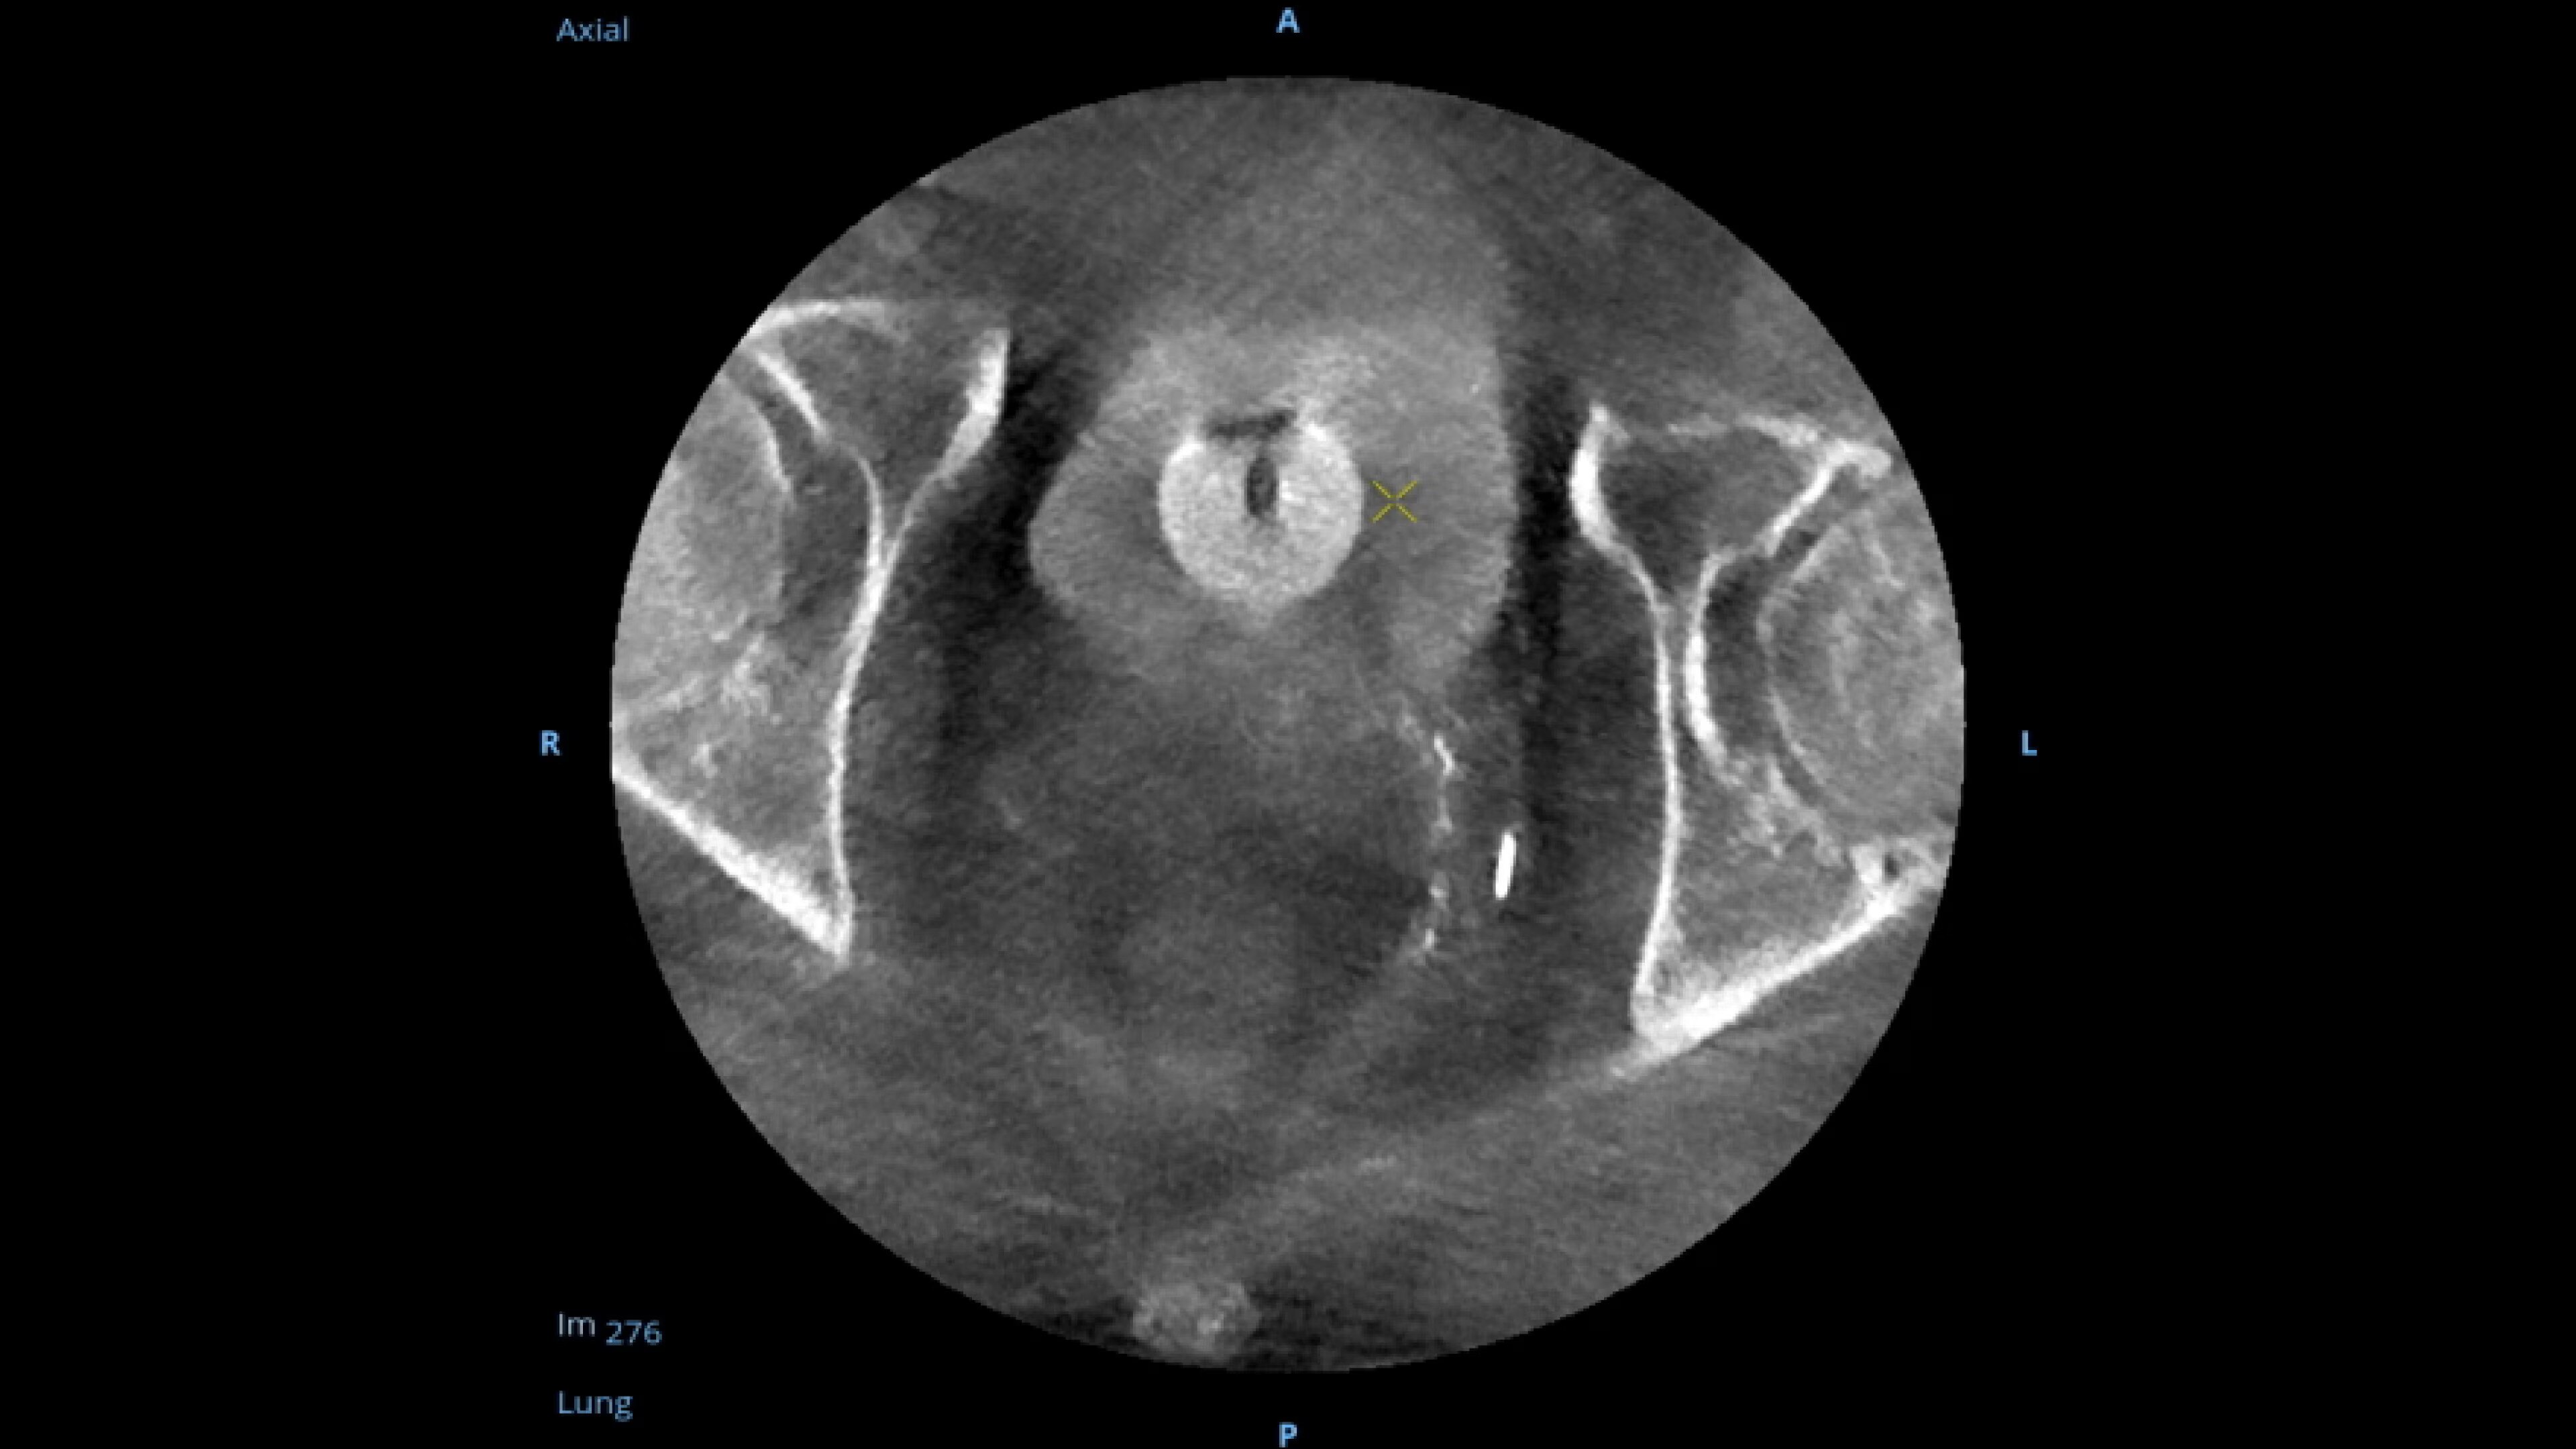

Precise

When visual confirmation during a procedure is desired, the

OEC 3D can provide 3D volumes with five perspectives.

Analyze CT-like images with the OEC 3D Volume Viewer which includes Multi-Oblique, Area Measure, Window Level/Window Width, rotate, zoom, and more for quick and comprehensive visualization.